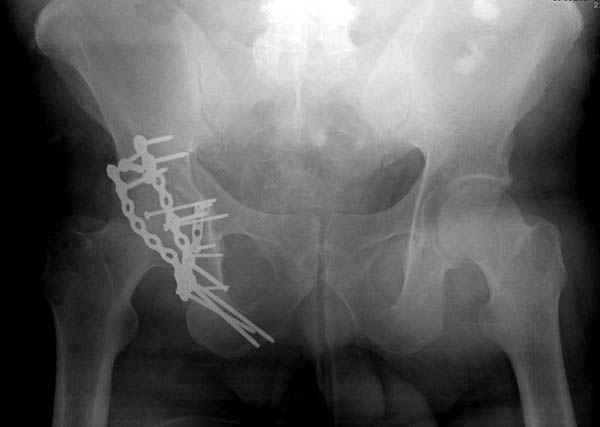

Дополнительно имеется перелом ацетабулума: задняя

колонна с полупоперечным переломом, и переломы костей лица.

На седьмой день зафиксирован перелом ацетабулума через задний доступ. Перед операцией для профилактики DVT, IVC фильтер, также получает Lovenox.

Извиняюсь за качества снимков, обычный больной в 300 фунтов, портативным ренген аппаратом не пробить.